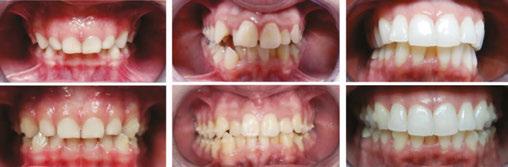

The following is a truly successful tooth story that outlines a scenario of a very scary moment for both mother and child, and how my team and I were able to put things back together as if no trauma happened at all.

A teenager’s avulsion tooth story

This 14-year-old boy was play-fighting with his brother in the kitchen with a broom. That broom hit him in the face and knocked out his front teeth.

Luckily, the young boy was undergoing orthodontic treatment so the avulsed teeth remained in the oral cavity. As you can see from the clinical photograph in Figure 1, teeth Nos. 8, 9, and 10 would not have remained in the mouth if the orthodontic wire was not in place.

There was some sealer extrusion at the apex of these teeth (Figure 7), especially 10, but this was due to the inflammatory resorption occurring at the apex as a result of the trauma, which started to eat away the apical stop. I am confident that, over time, this sealer will resorb away, and this extrusion should not impede the healing at all. Figure 8 is the final outcome of the case.

And now that the patient is stable, he can go back into his brackets and orthodontic wire. Figure 9 is him 6 months later, and we will continue to follow him up for the next 5 years.

Figures 9A-9B